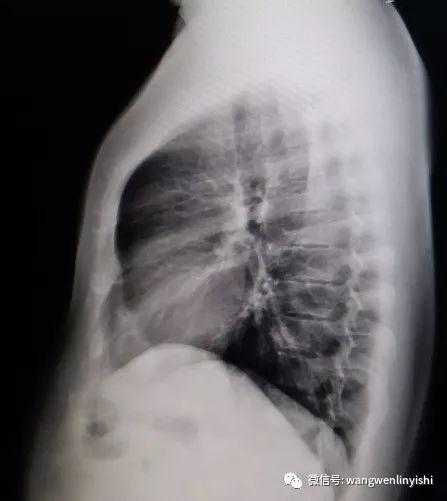

The upper part of the patient’s chest wall is protruded as a whole, coupled with depressions in the central and lower regions, presenting a classic example of Wenlin chest.

Wenlin chest is a distinctive chest wall deformity that was often mistakenly identified as pectus carinatum in the past. However, unlike PC, which is characterized by a single protrusion, Wenlin chest involves both protrusions and depressions, classifying it as a kind of complex chest wall deformities. This malformation can not be corrected by traditional surgeries that work for PC. Notably, the depression in Wenlin chest is only apparent in comparison to the protrusion of the upper chest wall, without significantly compressing the patient’s heart.